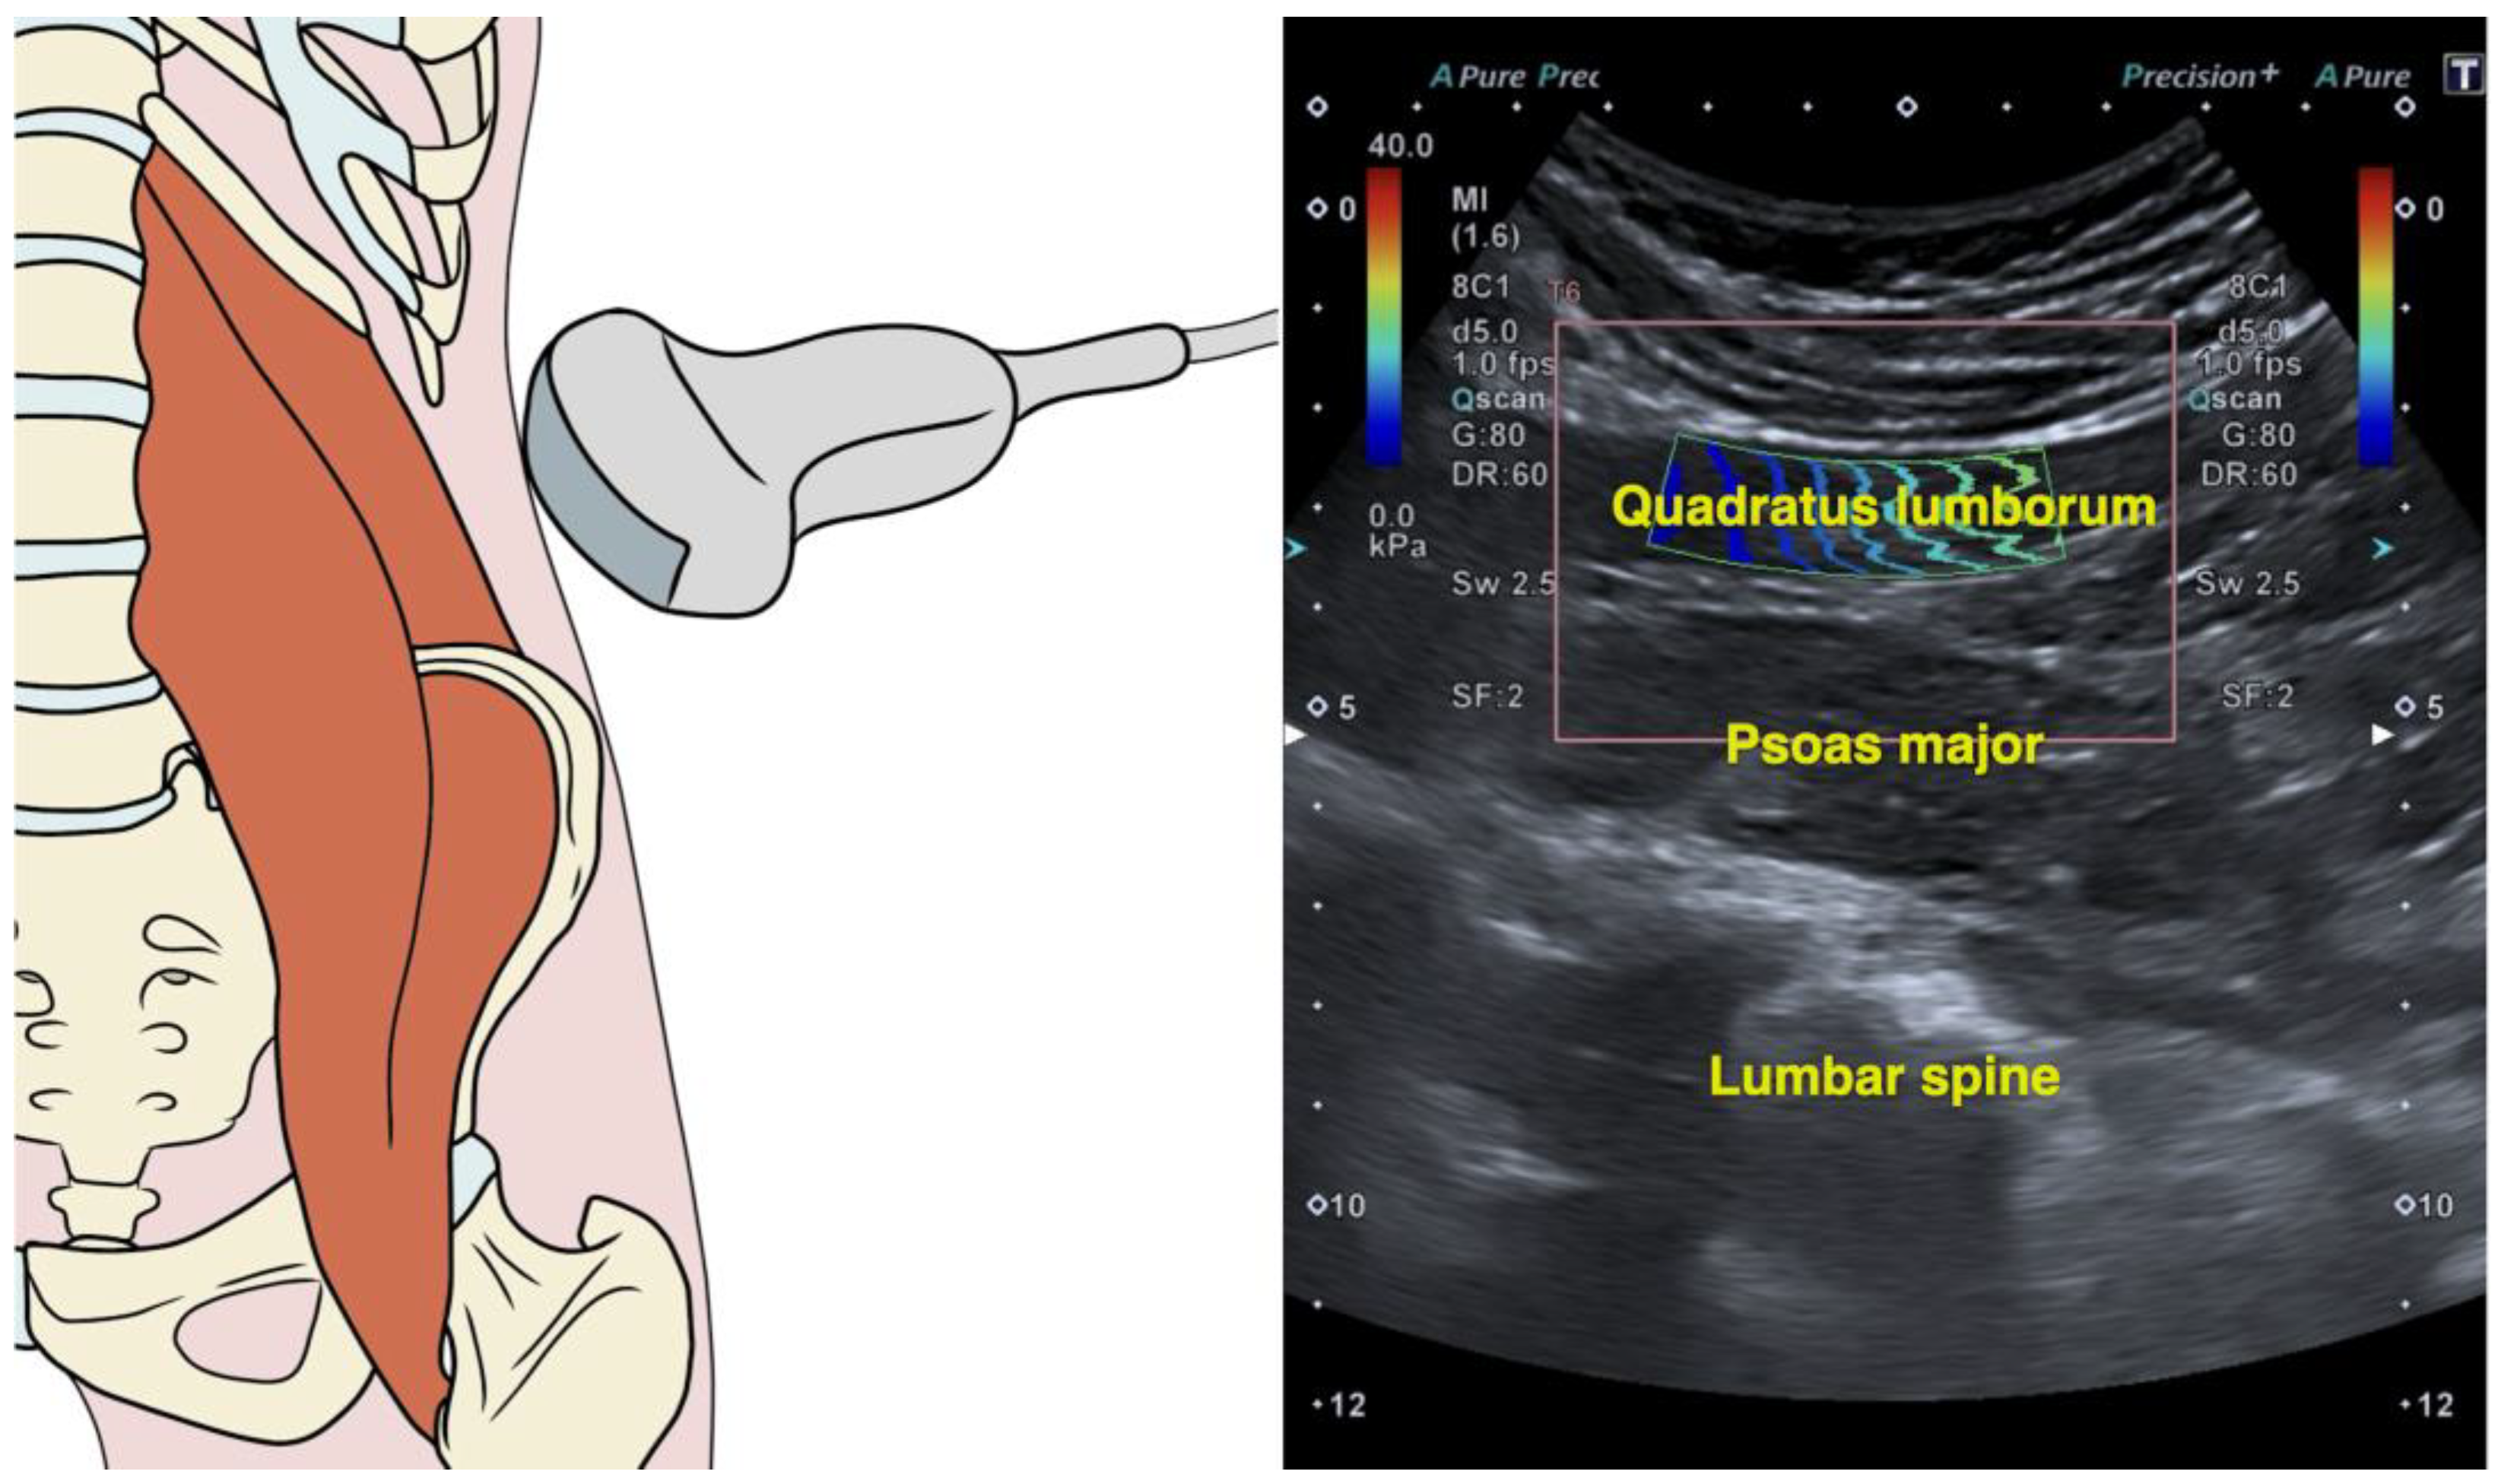

2.4. Quadratus Lumborum Muscle Stiffness